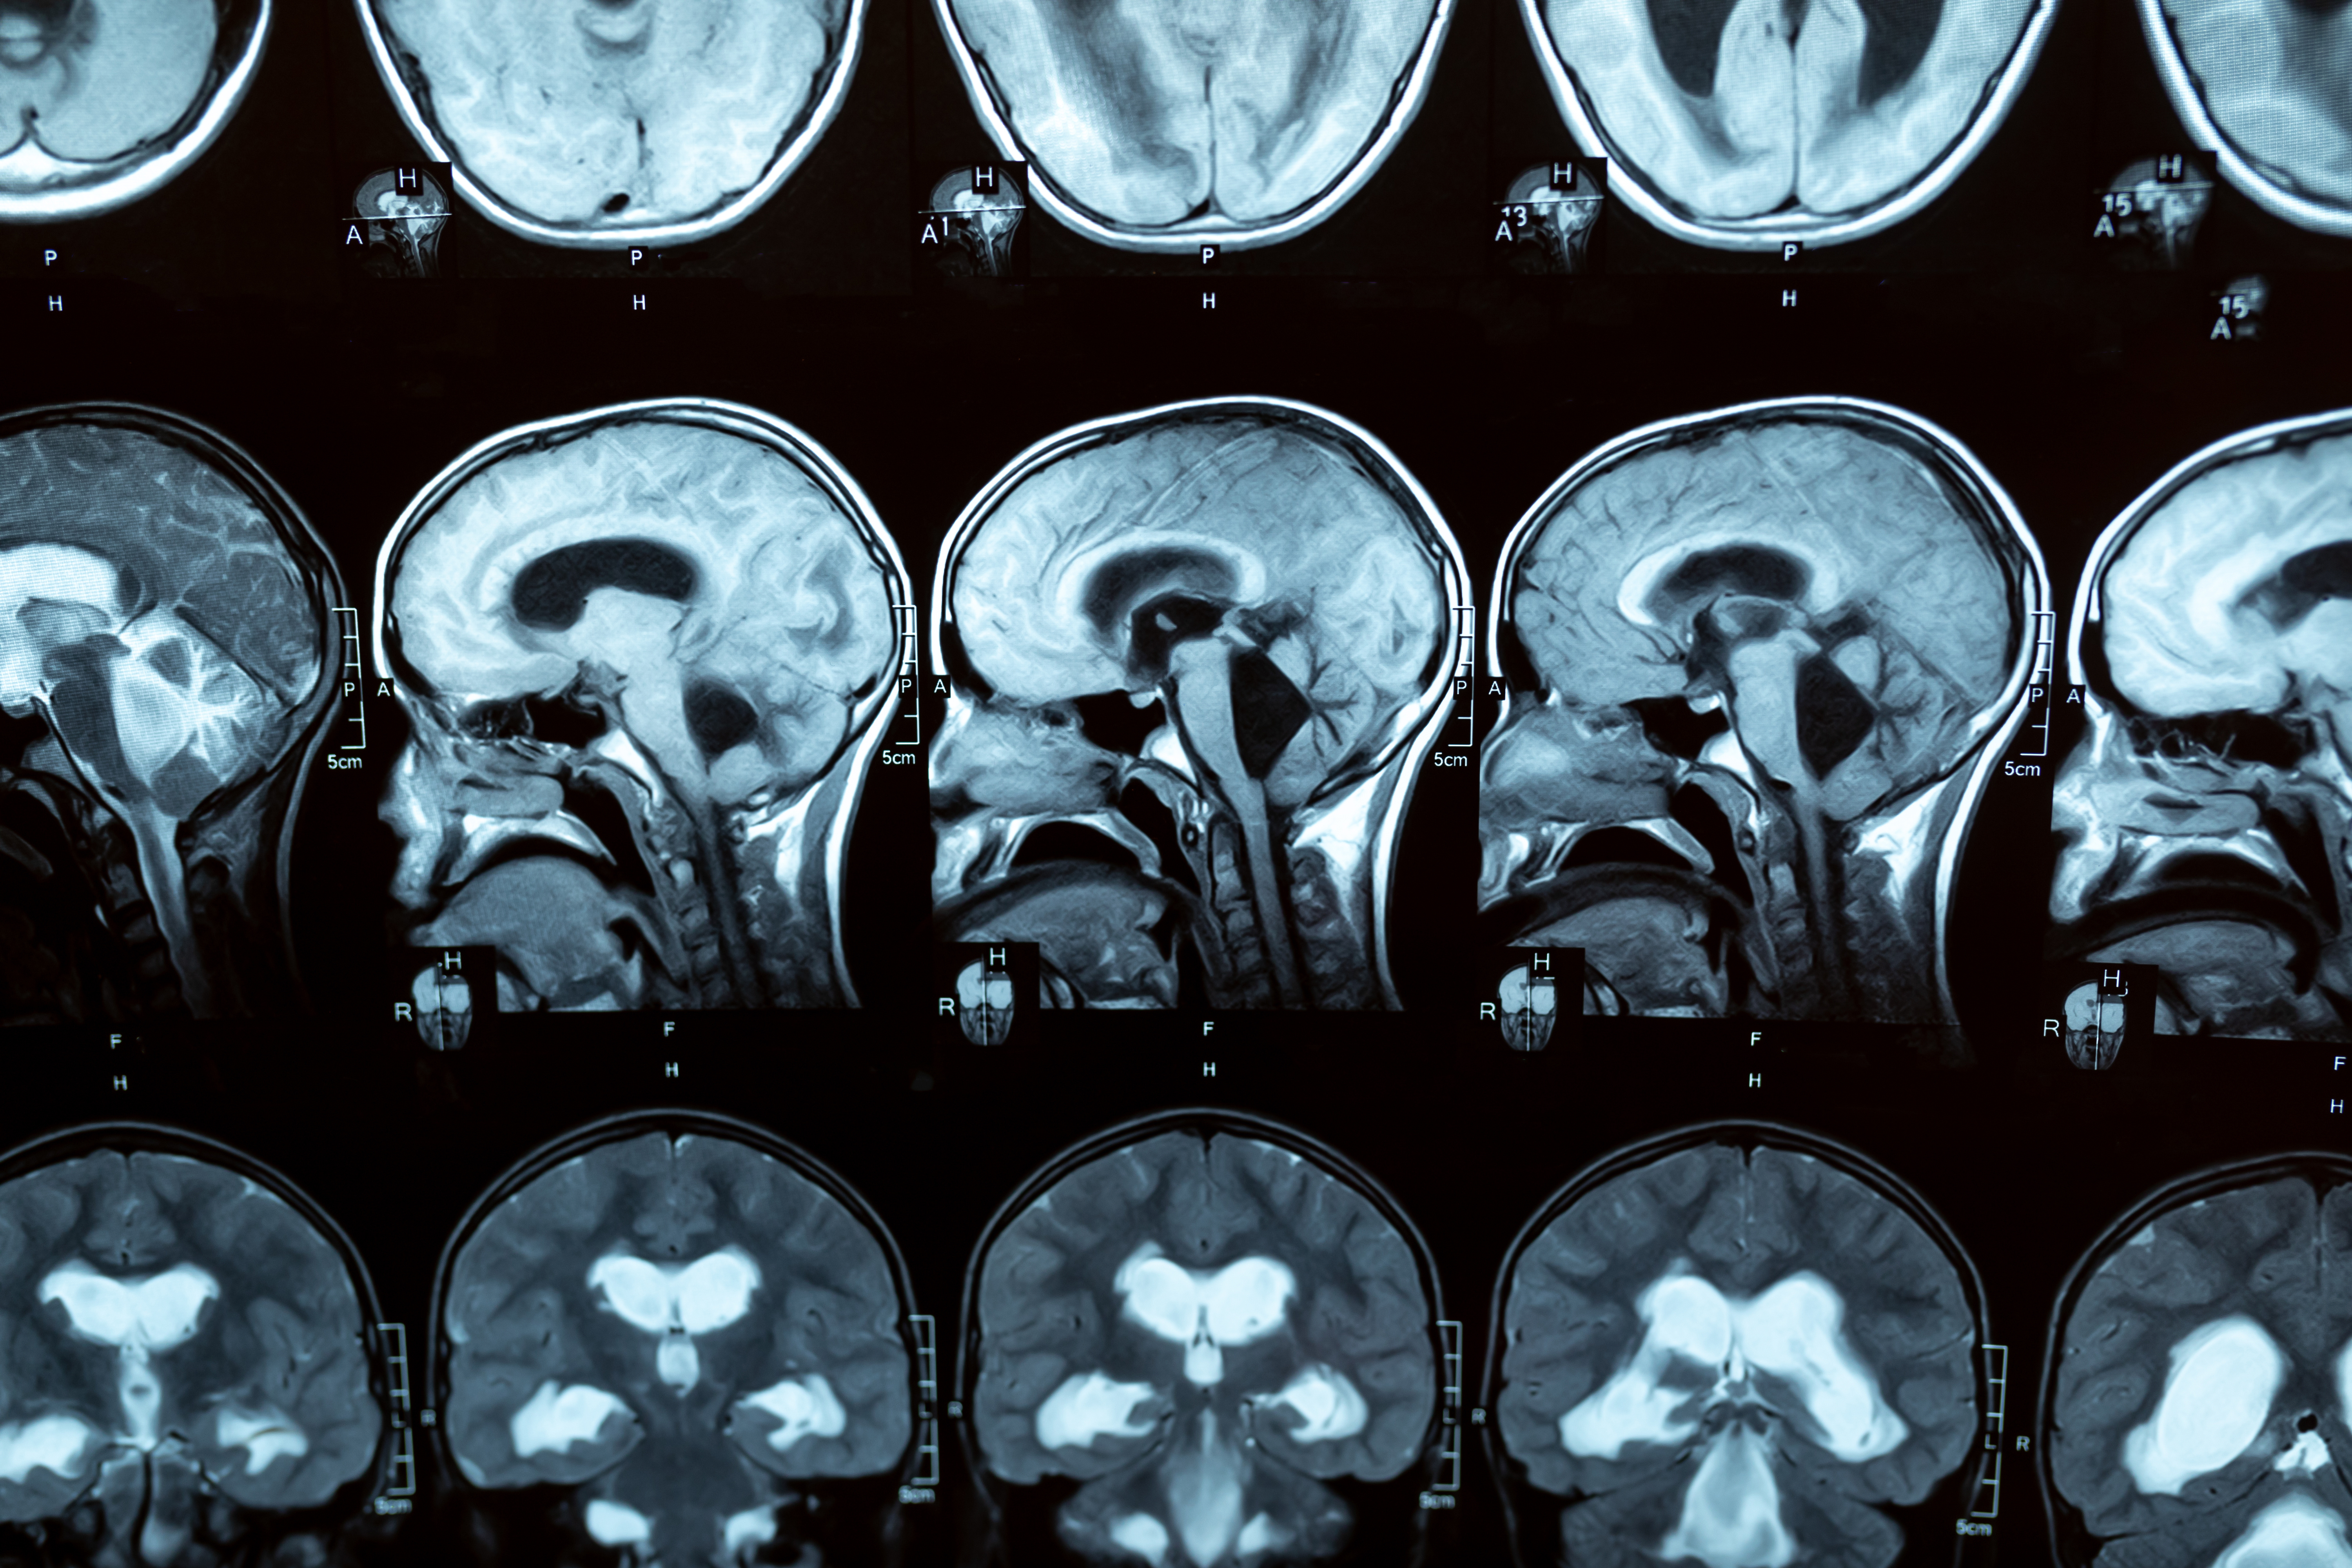

L'autisme n'est pas lié à un déclin cognitif accru avec l'âge, précise cette équipe de neuroscientifiques de l’University College London (UCL). La recherche, publiée dans la revue The Gerontologist, révèle qu'il n'existe aucune différence au fil du temps entre la mémoire de travail des personnes âgées présentant un trouble du spectre autistique (TSA) et des témoins neurotypiques.

C’est la première étude à explorer le taux de déclin de la mémoire de travail spatiale lié à l'âge chez des personnes plus âgées et autistes. L’un des auteurs principaux, le professeur Joshua Stott de l’UCL rappelle : « L'autisme est un trouble neurodéveloppemental associé à des différences dans la communication sociale et à des schémas répétitifs de comportements sensorimoteurs. On sait que les personnes autistes présentent souvent des différences cognitives par rapport aux personnes non autistes. Se pose donc la question de savoir si un trouble neurodéveloppemental comme l'autisme peut influencer le risque de déclin cognitif lié à l'âge, et potentiellement de démence ».

La mémoire de travail spatiale permet de mémoriser et d'utiliser des informations sur l'emplacement et la disposition des objets. Elle est généralement utilisée pour des tâches impliquant la navigation dans l'espace ou l'organisation d'objets. Avec l'âge, la mémoire de travail spatiale peut parfois perdre de son efficacité, ce qui constitue un marqueur intéressant de déclin cognitif. Ce déclin peut faire partie du vieillissement normal, mais il est accéléré et plus prononcé dans des maladies comme la maladie d'Alzheimer.

La mémoire de travail spatiale peut également être affectée chez les personnes autistes, notamment pour les tâches impliquant la mémorisation et l'organisation d'informations visuelles. Par conséquent, la question de savoir si l'autisme entraîne un risque accru de déclin cognitif et de démence future est toujours débattue.